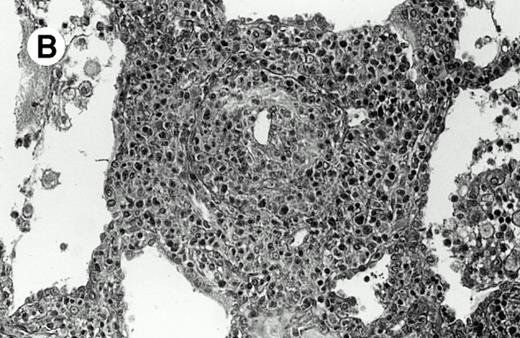

Three cases (cases no. 1 to 3) were located in the nasal cavity. The neoplastic infiltrate consisted of medium and/or large pleomorphic lymphoid cells (Fig 1)intermingled with variable numbers of small lymphoid cells, plasma cells, eosinophils, and histiocytes. Features of angiocentrism and angioinvasion, epitheliotropism, and areas of necrosis were observed in all three cases. Patient no. 4 presented with disease restricted to the lung and an open-lung biopsy was available. The neoplastic infiltrate was composed of large atypical lymphoid cells and was predominantly interstitial without extensive destruction of the normal architecture. Features of angiocentrism, angioinvasion, and epitheliotropism were present (Fig 2A and B). Case no. 5 involved the larynx, extending to the piriform sinus, the ventricle, and the arytenoid. One month later, the lymphoma disseminated to the subcutaneous tissue in the spinal region and biopsy specimens from both sites were available. The neoplastic cells were medium and large, with abundant clear cytoplasm and slightly irregular nuclei with dense chromatin. Epitheliotropism was present in the larynx mucosa. Small foci of necrosis and angiocentrism were seen without angioinvasion. Three patients presented with cutaneous disease. Cases no. 6 and 7 were comparable, as both histories started with necrotic subcutaneous nodules of the thigh, which on histologic analysis were characteristic of cytophagic histiocytic panniculitis without evidence of lymphoma (Fig 3A). Second excisional biopsies of cutaneous nodules obtained 7 and 5 months later, respectively, showed characteristic features of lymphoma in both cases (Fig 3B). However, in case no. 6, skin biopsy specimens showed an epidermotropic PML lymphoma extending to the dermis and the subcutaneous tissue, whereas in case no. 7, the neoplastic infiltrate consisted of a PSC confined to the subcutaneous tissue, admixed with benign histiocytes that showed phagocytosis. Patient no. 8 presented with recurrent skin lesions with spontaneous remission over a period of 10 years. The initial skin biopsies demonstrated an intense epidermotropic neoplastic infiltrate that extended to the superficial and deep dermis composed of atypical PML cells. All cutaneous cases displayed features of angiocentrism, but angioinvasion was observed only in case no. 6 and foci of necrosis in cases no. 6 and 8.

Subcutaneous γδ T-cell lymphoma (case no. 6). (A) Initial biopsy sample shows characteristic features of cytophagic histiocytic panniculitis without evidence of lymphoma cells; (B) second biopsy performed 7 months later demonstrates involvement of the subcutaneous tissue by a pleomorphic γδ T-cell lymphoma (hematoxylin-eosin stain).